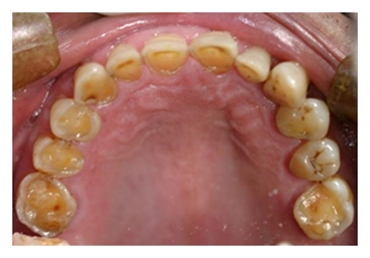

The stomach acid from GERD can eat away the enamel on teeth. Enamel is the outermost layer of teeth meant to protect the soft and sensitive inner layers. The pattern of erosion from acid reflux often starts with the back teeth and the inside surfaces of teeth. But in some cases, the chewing surfaces of the teeth can also suffer damage. Unfortunately, enamel loss is permanent and can increase the risk of dental decay.